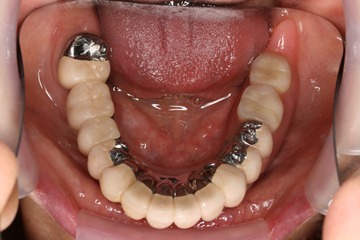

今回は昨年7月にご紹介したリーゲルテレスコープ義歯の完成ケースをご報告します。

テレスコープとは望遠鏡の意味で、内側の筒状の冠を歯にかぶせ、外側の筒を入れ歯にしたものです。また、リーゲルとはかんぬき(閂)の意味で、内側の筒と外側の筒(入れ歯)をレバーにより固定するものです。

この入れ歯は、自分で装着したり、外したりできるものですが、どちらかと言うと入れ歯と言うよりは、固定式のブリッジに近いかもしれません。そのくらい強く噛むことが出来、硬い食べ物を味わうことができます。

また、お口の中でコンパクトにまとまって、邪魔になりません。バネがないので、食べ物が引っかかったり、頬や舌が荒れたりしません。バネがないので、笑った時に見えるのは、白い歯だけです。

入れ歯を装着し、レバーをロックして動かないようにしたところです。